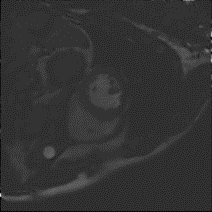

Although supervised deep-learning has achieved promising performance in medical image segmentation, many methods cannot generalize well on unseen data, limiting their real-world applicability. To address this problem, we propose a deep learning-based Bayesian framework, which jointly models image and label statistics, utilizing the domain-irrelevant contour of a medical image for segmentation. Specifically, we first decompose an image into components of contour and basis. Then, we model the expected label as a variable only related to the contour. Finally, we develop a variational Bayesian framework to infer the posterior distributions of these variables, including the contour, the basis, and the label. The framework is implemented with neural networks, thus is referred to as deep Bayesian segmentation. Results on the task of cross-sequence cardiac MRI segmentation show that our method set a new state of the art for model generalizability. Particularly, the BayeSeg model trained with LGE MRI generalized well on T2 images and outperformed other models with great margins, i.e., over 0.47 in terms of average Dice. Our code is available at https://zmiclab.github.io/projects.html.